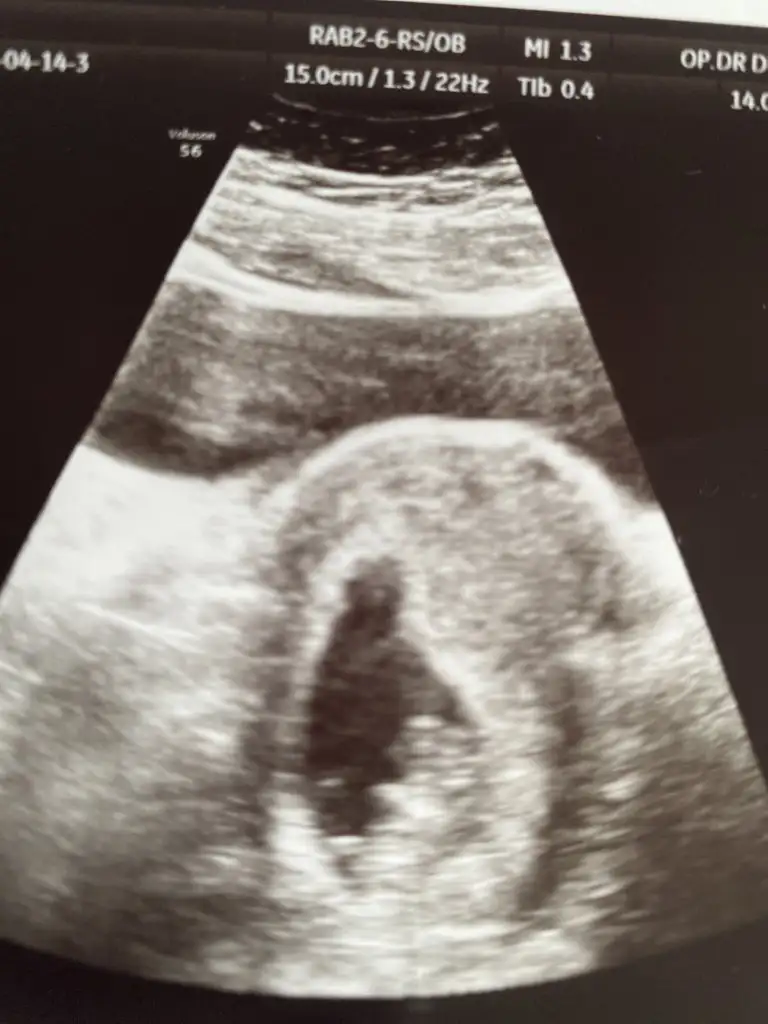

Benimde karından ultrason tahmin yapabilir misiniz şimdiden çok teşekkür ederim ❤️

• IMG-20210421-WA0012.webp

IMG-20210421-WA0012.webp

23,3 KB · Görüntüleme: 83